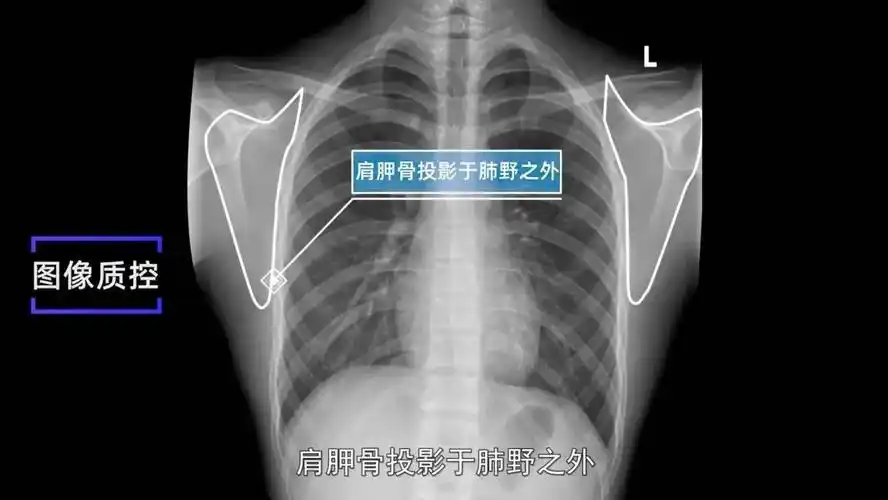

肩胛骨投影于肺野之外.3. 肺尖充分显示.2.